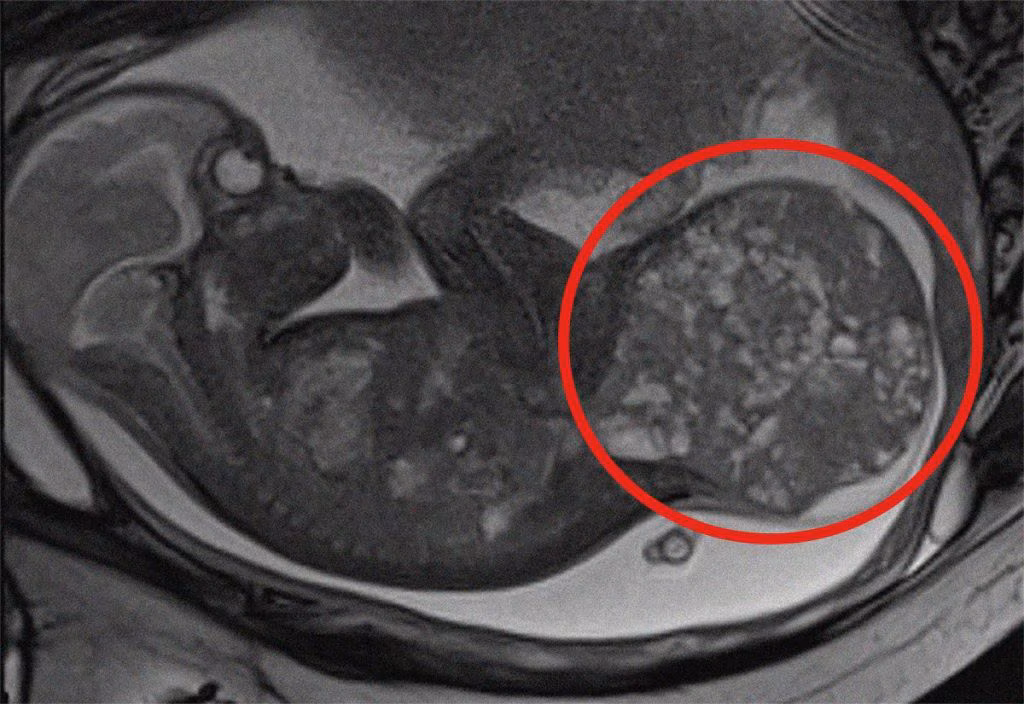

La procedura intrauterina è stata eseguita con estrema precisione per garantire la sicurezza della gestante e del feto. La diagnosi e il monitoraggio sono stati effettuati tramite risonanza magnetica fetale, che ha evidenziato chiaramente la posizione e le dimensioni della massa tumorale.

La rara patologia diagnosticata alla bambina è un teratoma sacro-coccigeo, una neoplasia che si sviluppa nella parte terminale della colonna vertebrale. Questo tipo di tumore, che colpisce circa un neonato ogni 35.000-40.000 nati vivi, è generalmente benigno, ma può causare complicazioni gravi per il feto, come scompenso cardiaco, idrope fetale e persino morte intrauterina.